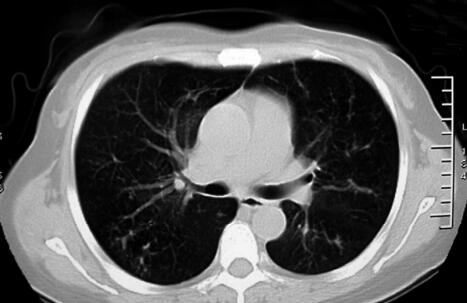

治疗1周后,患者体温恢复正常,气短较前好转,肺部干鸣音消失,仍可闻及散在湿啰音,胸部CT示胸腔积液吸收,斑片影无明显变化(图3)。治疗1个月后,患者无临床症状,复查血常规正常;复查胸部CT示双肺斑片影较前明显吸收(图4)。

图3